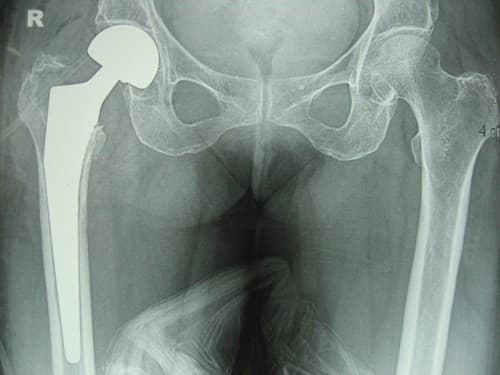

Phẫu thuật thay khớp háng được thực hiện để để thay thế phần khớp bị hư hỏng, tổn thương bằng khớp nhân tạo nhằm giảm bớt đau đớn, khôi phục lại khả năng vận động khớp háng.

Trong phẫu thuật thay khớp háng, người bệnh sẽ được gây mê hay gây tê tủy sống. Bác sĩ sẽ rạch một đường mổ dọc bên háng, tách cơ nối kết với phần đỉnh của xương đùi, và mở khớp háng. Kéo chỏm của xương đùi (phần đầu của xương đùi) ra khỏi phần ổ cối (phần xương chậu). Phần chỏm của xương đùi bị cắt và phần thay thế nhân tạo được lắp vào.

Bác sĩ chuẩn bị bề mặt ổ cối, nếu nó mòn, sẽ được thay thế bằng kim loại hay plastic. Nắn phần chỏm mới của xương đùi vào ổ cối. Hai đường ống có thể được thêm vào giúp thoát dịch hay máu từ phần khớp mới. Bác sĩ sẽ khâu các cơ ở đầu xương đùi và khâu vết mổ phía bên háng lại.